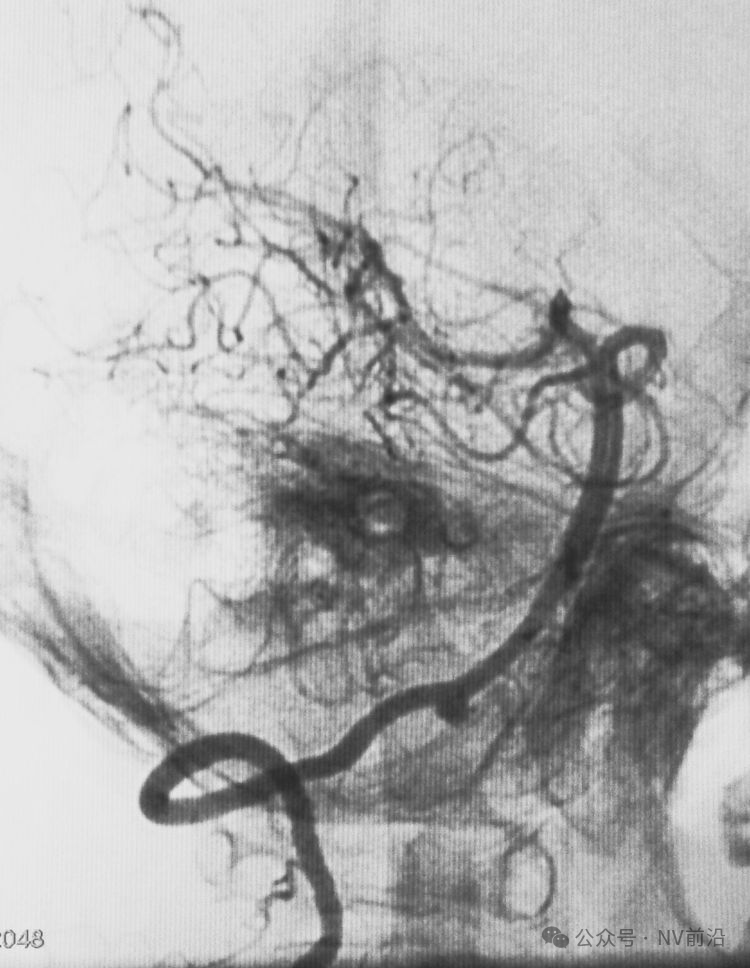

病例二,右侧椎动脉V4段夹层动脉瘤,以头痛入院,21个月前有SAH史。

右椎动脉造影三维重建

Echelon 10微导管头无论塑成C形还是S形,均无法稳定于动脉瘤腔内,遂使用回马枪技术,使微导管成襻通过,管头折返入瘤腔。